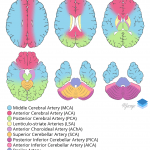

- Asymmetrically hyperdense appearance of the right internal carotid artery terminus and proximal right MCA

Asymmetrically hyperdense appearance of the right internal carotid artery terminus and proximal right MCA, which may be artifactual or could represent thrombus. Recommend correlation with CTA.